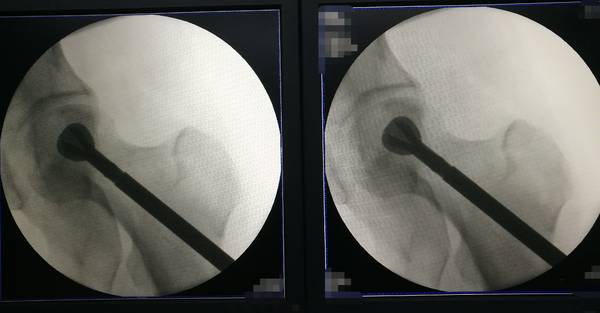

骨科机器人辅助定位

股骨头坏死骨刮除

松质骨,人工骨混合植入

游离腓骨段植入

吻合血管重建血运

IMG_20190115_095822.jpg

IMG_20190115_100704.jpg

IMG_20190115_100710.jpg

IMG_20190115_112818.jpg